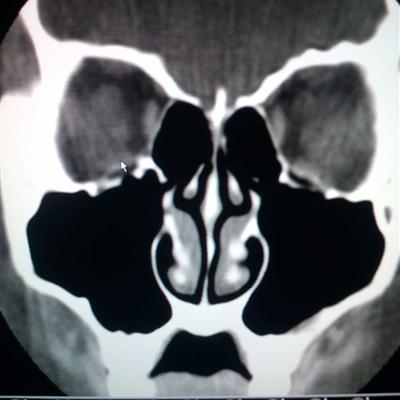

Nasopharyngeal carcinoma, a difficult to cure respiratory cancer. At present, the environment around people has caused different degrees of damage to our nose, throat and throat. Next, I would like to share what nutrients can we eat for nasal cancer?. Hope to help you.

What nutrition can nasal cavity cancer eat?